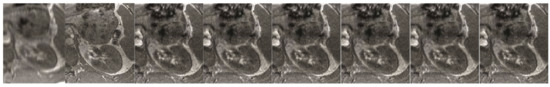

Figure 7. The brain imaging results. From left to right: A: Image reconstructed from partially sampled PROPELLER blade, B:Cartesian sampling grid without image registration applied (with no downsampling applied), C: B-spline Cubic interpolation, D: Non-Rigid Multi-Modal 3D Medical Image Registration Based on Foveated Modality Independent Neighbourhood Descriptor [45], E: Enhanced deep residual networks for single image super-resolution [14], F: Image super-resolution using very deep residual channel attention networks [16], G: Residual dense network for image super-resolution [15], H: super-resolution with proposed sampling scheme and motion compensation (the proposed algorithm). Compression ratio is 50%. Please see Table 2 for the PSNR values at other compression ratios.

In order to measure the performance of the proposed algorithm, both laboratory phantom studies and an in-vivo assessment were performed. The purpose of the experiment was to compare the effectiveness of various ways of obtaining a compressively-sensed input. In a study of the effects of various compressed-sensing ratio on test performance, the test performance of the proposed Super-Resolution Image Reconstruction method was tested. Moreover, several MRI k-space sampling patterns have been compared. Figure 5, Figure 6, Figure 7, Figure 8, Figure 9, Figure 10, Figure 11, Figure 12, Figure 13, Figure 14, Figure 15, Figure 16, Figure 17, Figure 18, Figure 19, Figure 20, Figure 21 and Figure 22 show the achieved results. It must be emphasised that combining Compressed Sensing with Hermitian symmetry property, as well as Partial Fourier allows the shortening of k-space filling when compared to the different k-space sampling schemes, see Figure 1.